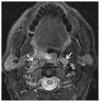

Cross-sectional imaging plays an important role in the evaluation of the retropharyngeal space (RPS) and the prevertebral space (PVS). Because of their deep location within the neck, lesions arising within these spaces are difficult, if not impossible, to evaluate on clinical examination. This article details the cross-sectional anatomy and imaging appearances of primary and secondary diseases involving the RPS and PVS, including metastasis and spread from adjacent spaces. The role of image-guided biopsy is also discussed.